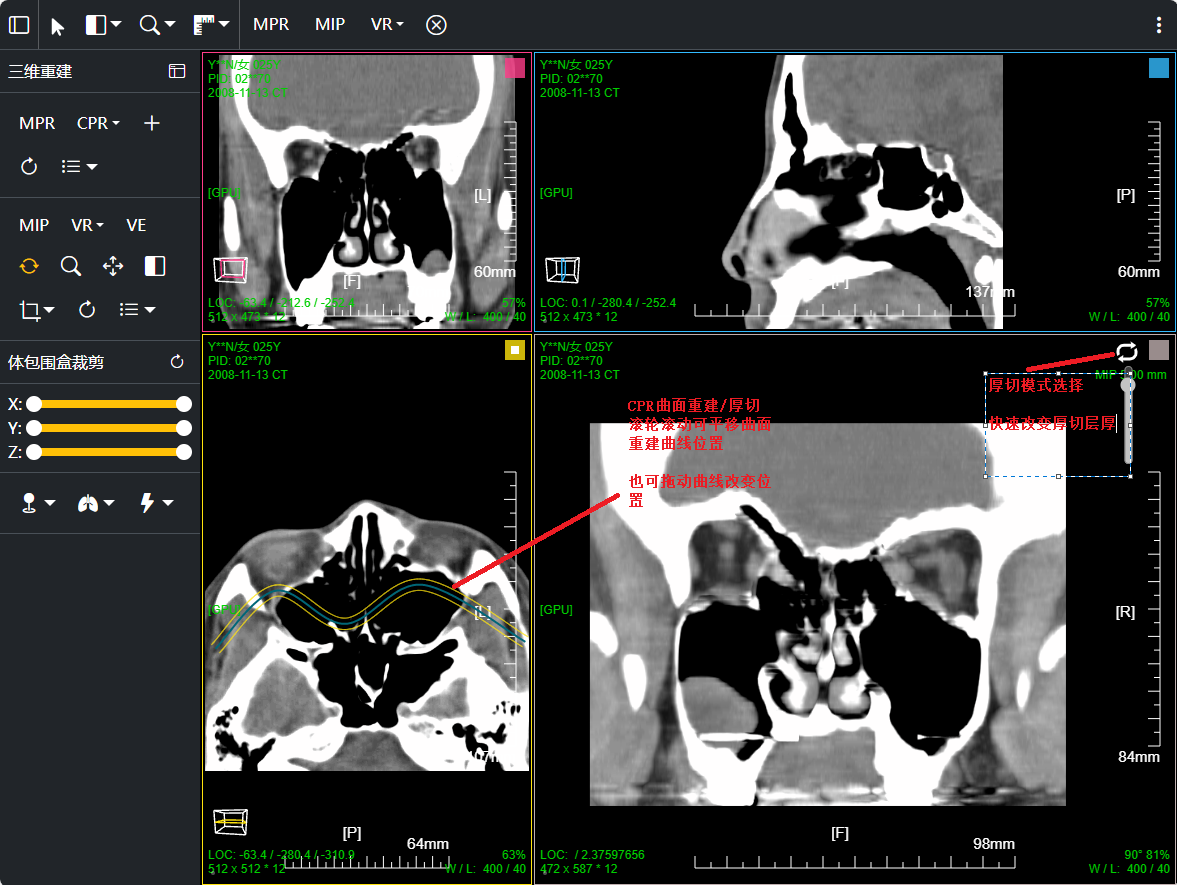

三维:MPR多平面重建(支持任意旋转)、CPR任意曲线切面重建、MIP最大密度、VR容积重建、VE虚拟内窥;任意三维裁剪、一键去床、一键去头骨、快速旋转、厚切MPR(最大密度/最小密度/均值/VR); 手工/半自动分割,分割目标三维渲染; 肋骨CPR拉伸渲染、牙神经管渲染、血管CPR拉直渲染等

八、三维浏览功能操作和截图

左键双击MPR窗口可在MPR三窗口和1x1窗口间切换;三维渲染窗口左键双击在在1x1视图模式和当前视图模式切换

点击MPR窗口右上角颜色块可AXIS轴位、CORO冠位、SAGI矢位切片切换

CPR曲面重建 、厚切曲面;